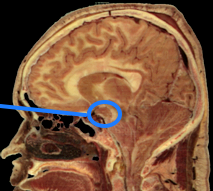

A. Brain: Interconnected neural circuits in the hypothalamus

- Lateral Hypothalamus (LH): Initiate eating

- Ventromedial Hypothalamus (VMH): Stop eating

- Arcuate Nucleus: Dual set of neurons: start & stop

- Paraventricular Hypothalamus (PVH): modulation of hunger